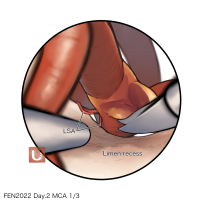

FEN2022シリーズ